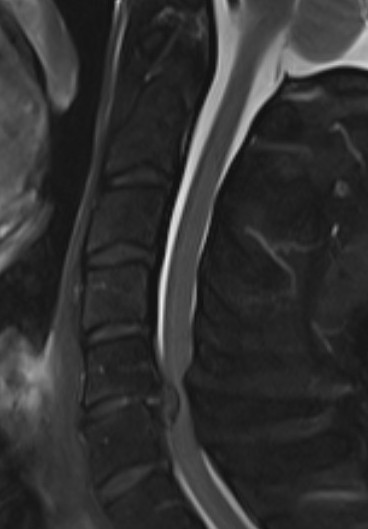

MRI

1. Space available for cord (SAC)

- Sagittal diameter of spinal canal - sagittal diameter spinal cord

- normal (17mm)

- relative (13mm)

- absolute stenosis (10mm)

Reduced by disc / osteophytes / OPLL / deformity / instability

Single level stenosis Double level stenosis Multi-level stenosis

4. Evidence of cord edema / spinal cord damage

- often seen after acute injury in setting of stenosis

- best seen on STIR MRI

Spinal cord edema / injury